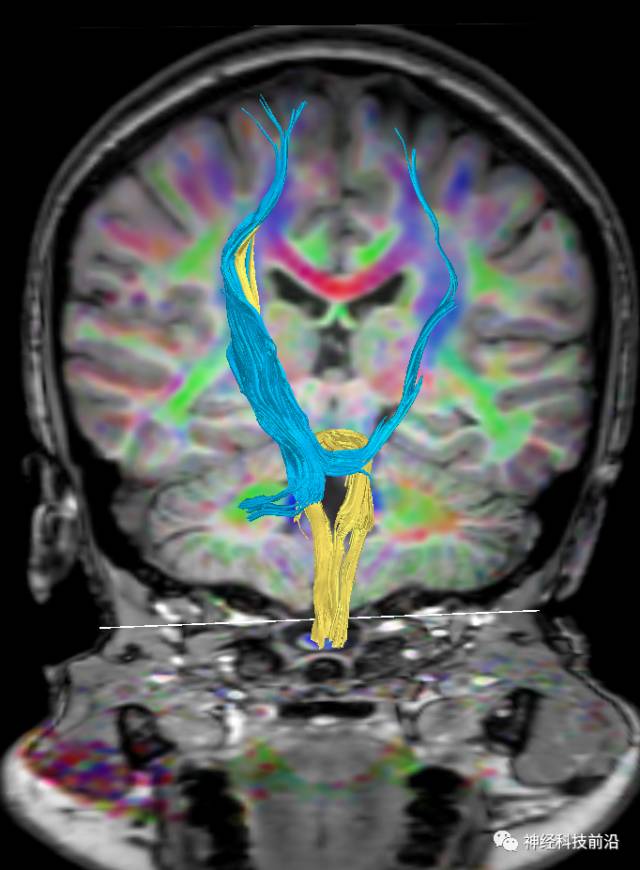

DTI原始图像与T1融合图像

下面为皮质脊髓束的走形及位置

皮质脊髓束与皮质脑桥束的关系毗邻